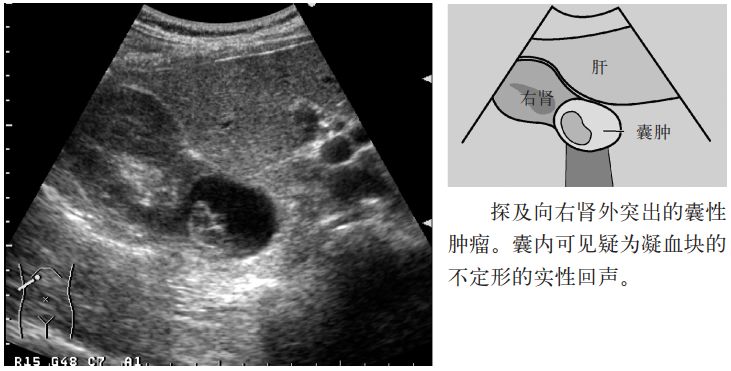

图4 肾囊肿(囊内出血)

图5 肾囊肿(囊内出血)

2.囊肿内出血时内部有回声,需要与囊肿内肿瘤鉴别。彩色多普勒检查可确认内部回声中有无血流信号。囊肿内出血时其内部无血流信号。